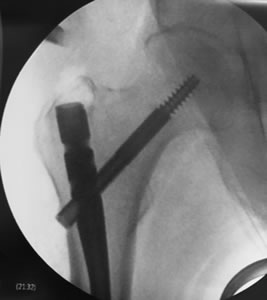

• Fijación de la fractura con tornillos, clavos endomedulares o placas

El objetivo de obtener una fijación interna rígida y estable de los fragmentos de la fractura, que permita al paciente pasar a la fase ambulatoria o al menos a una carga parcial del miembro operado en un corto período de tiempo.

La movilización es ventajosa para prevenir complicaciones pulmonares, trombosis venosas, úlceras por decúbito y deterioro general.